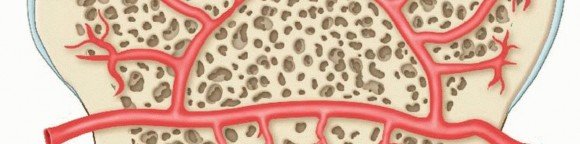

The epiphyseal artery supplies the epiphysis and secondary centers of ossification.

Repetitive microtrauma or a trauma in a growing child to one of these small end arteries with a tenuous blood supply can result in disruption of the vascular supply to the segment, with resultant development of an OCD

lesion20 (

FIG 4

).

The alteration of subchondral vascularity is precipitated by insult at a vulnerable point.

In juvenile cases, revascularization can occur.

In most situations, however, healing is inadequate, and persistent avascularity of the fragment, along with mechanical forces at the subchondral region, leads to articular surface fracture.

Synovial fluid pumped into the bone around the fragment via knee motion limits healing by preventing fibrin clot formation. The pressurized fluid can even erode bone and create a cystic defect. Loss of fragment stability results in loose body formation.

FIG 4 • Osteochondritis lesions can occur from an interruption of the epiphyseal blood supply to a specific area. (Adapted from Williams JS Jr, Bush-Joseph CA, Bach BR. Osteochondritis dissecans of the knee. Am J Knee Surg 1998;11:221-232.)